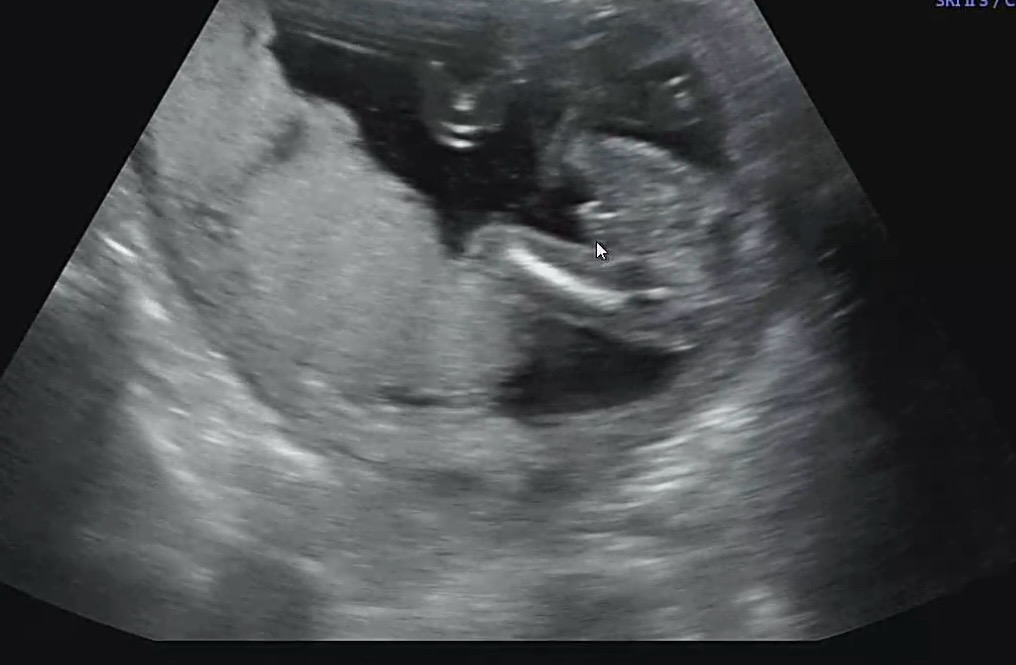

17주 2일차에 아들 확정 짓고 왔어요!🌶️ 늘 입덧과 두통을 달고살았고.. 그거외엔 이벤트가 없었어서, 전 첫째인데도 입덧하니 잘 있겟지~ 하며 4주를 궁금함만 가지고 ㅋㅋ 일에치여 살앗더니 검진날이었어요!! 남편도 딸 아들 아무나 와라! 였고 저도 아들 딸 상관없다! 하는 입장이었어서 오늘 확인했는데 바로 다리사이에 🌶️🌶️,, 선생님도 이게 고추에요 하는데 왜캐 ㅋㅋㅋㅋㅋ 전 기여운건지ㅎㅎ 여기는 딸맘들 많은거 같은데 아들맘도 많으신가요?ㅎㅎㅎ 갑자기 궁금하네요 아무튼 딸맘들 아들맘들 다 반가워요 우리 잘 품고있다 순산해요 😝😝